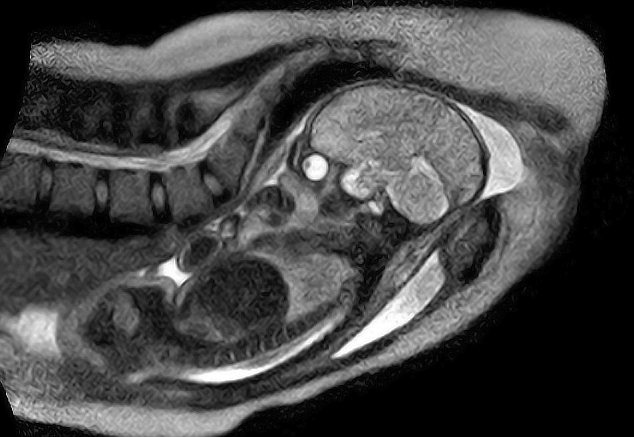

МРТ ребенка в утробе: что показывает снимок